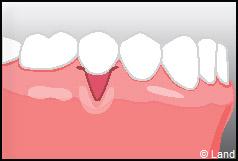

Les conséquences de cette mise à nu de la racine dentaire sont multiples, le patient peut présenter une hypersensibilité dentaire et l’aspect de ces récessions peut être inesthétique. Dans ce cas, la chirurgie muco-gingivale est recommandée et elle peut se faire de différentes façons.

LES TECHNIQUES SANS APPORT DE GENCIVE :

Elles font appel à des lambeaux de gencive restante à proximité des récessions, qui sont déplacés et repositionnés sur la récession.